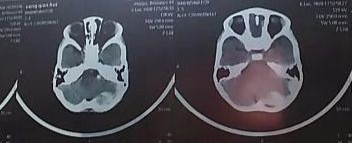

治疗前CT图片

3岁小孩,玩耍时跌倒头枕部着地受伤,致头疼不适,送去某医院求治,CT检查发现:左枕及小脑硬膜外血肿(图1-2)。该医院医生意见:开颅手术清除血肿。理论上讲,确实有手术指征!但是这个病人家属担心开颅手术风险太大,对小孩影响不好,拒绝手术。后来经过中西医结合保守治疗(20天左右),逐渐好转并完全治愈(图3-4)。有时候病人的治疗需要根据病情综合考虑,如果没有慎重考虑,匆忙做了手术,可能符合治疗原则,但是给病人带来了不必要的痛苦,增加了病人的经济负担和心理创伤!当然这更需要医生的诊疗技术、责任心和担当![加油][加油][加油]